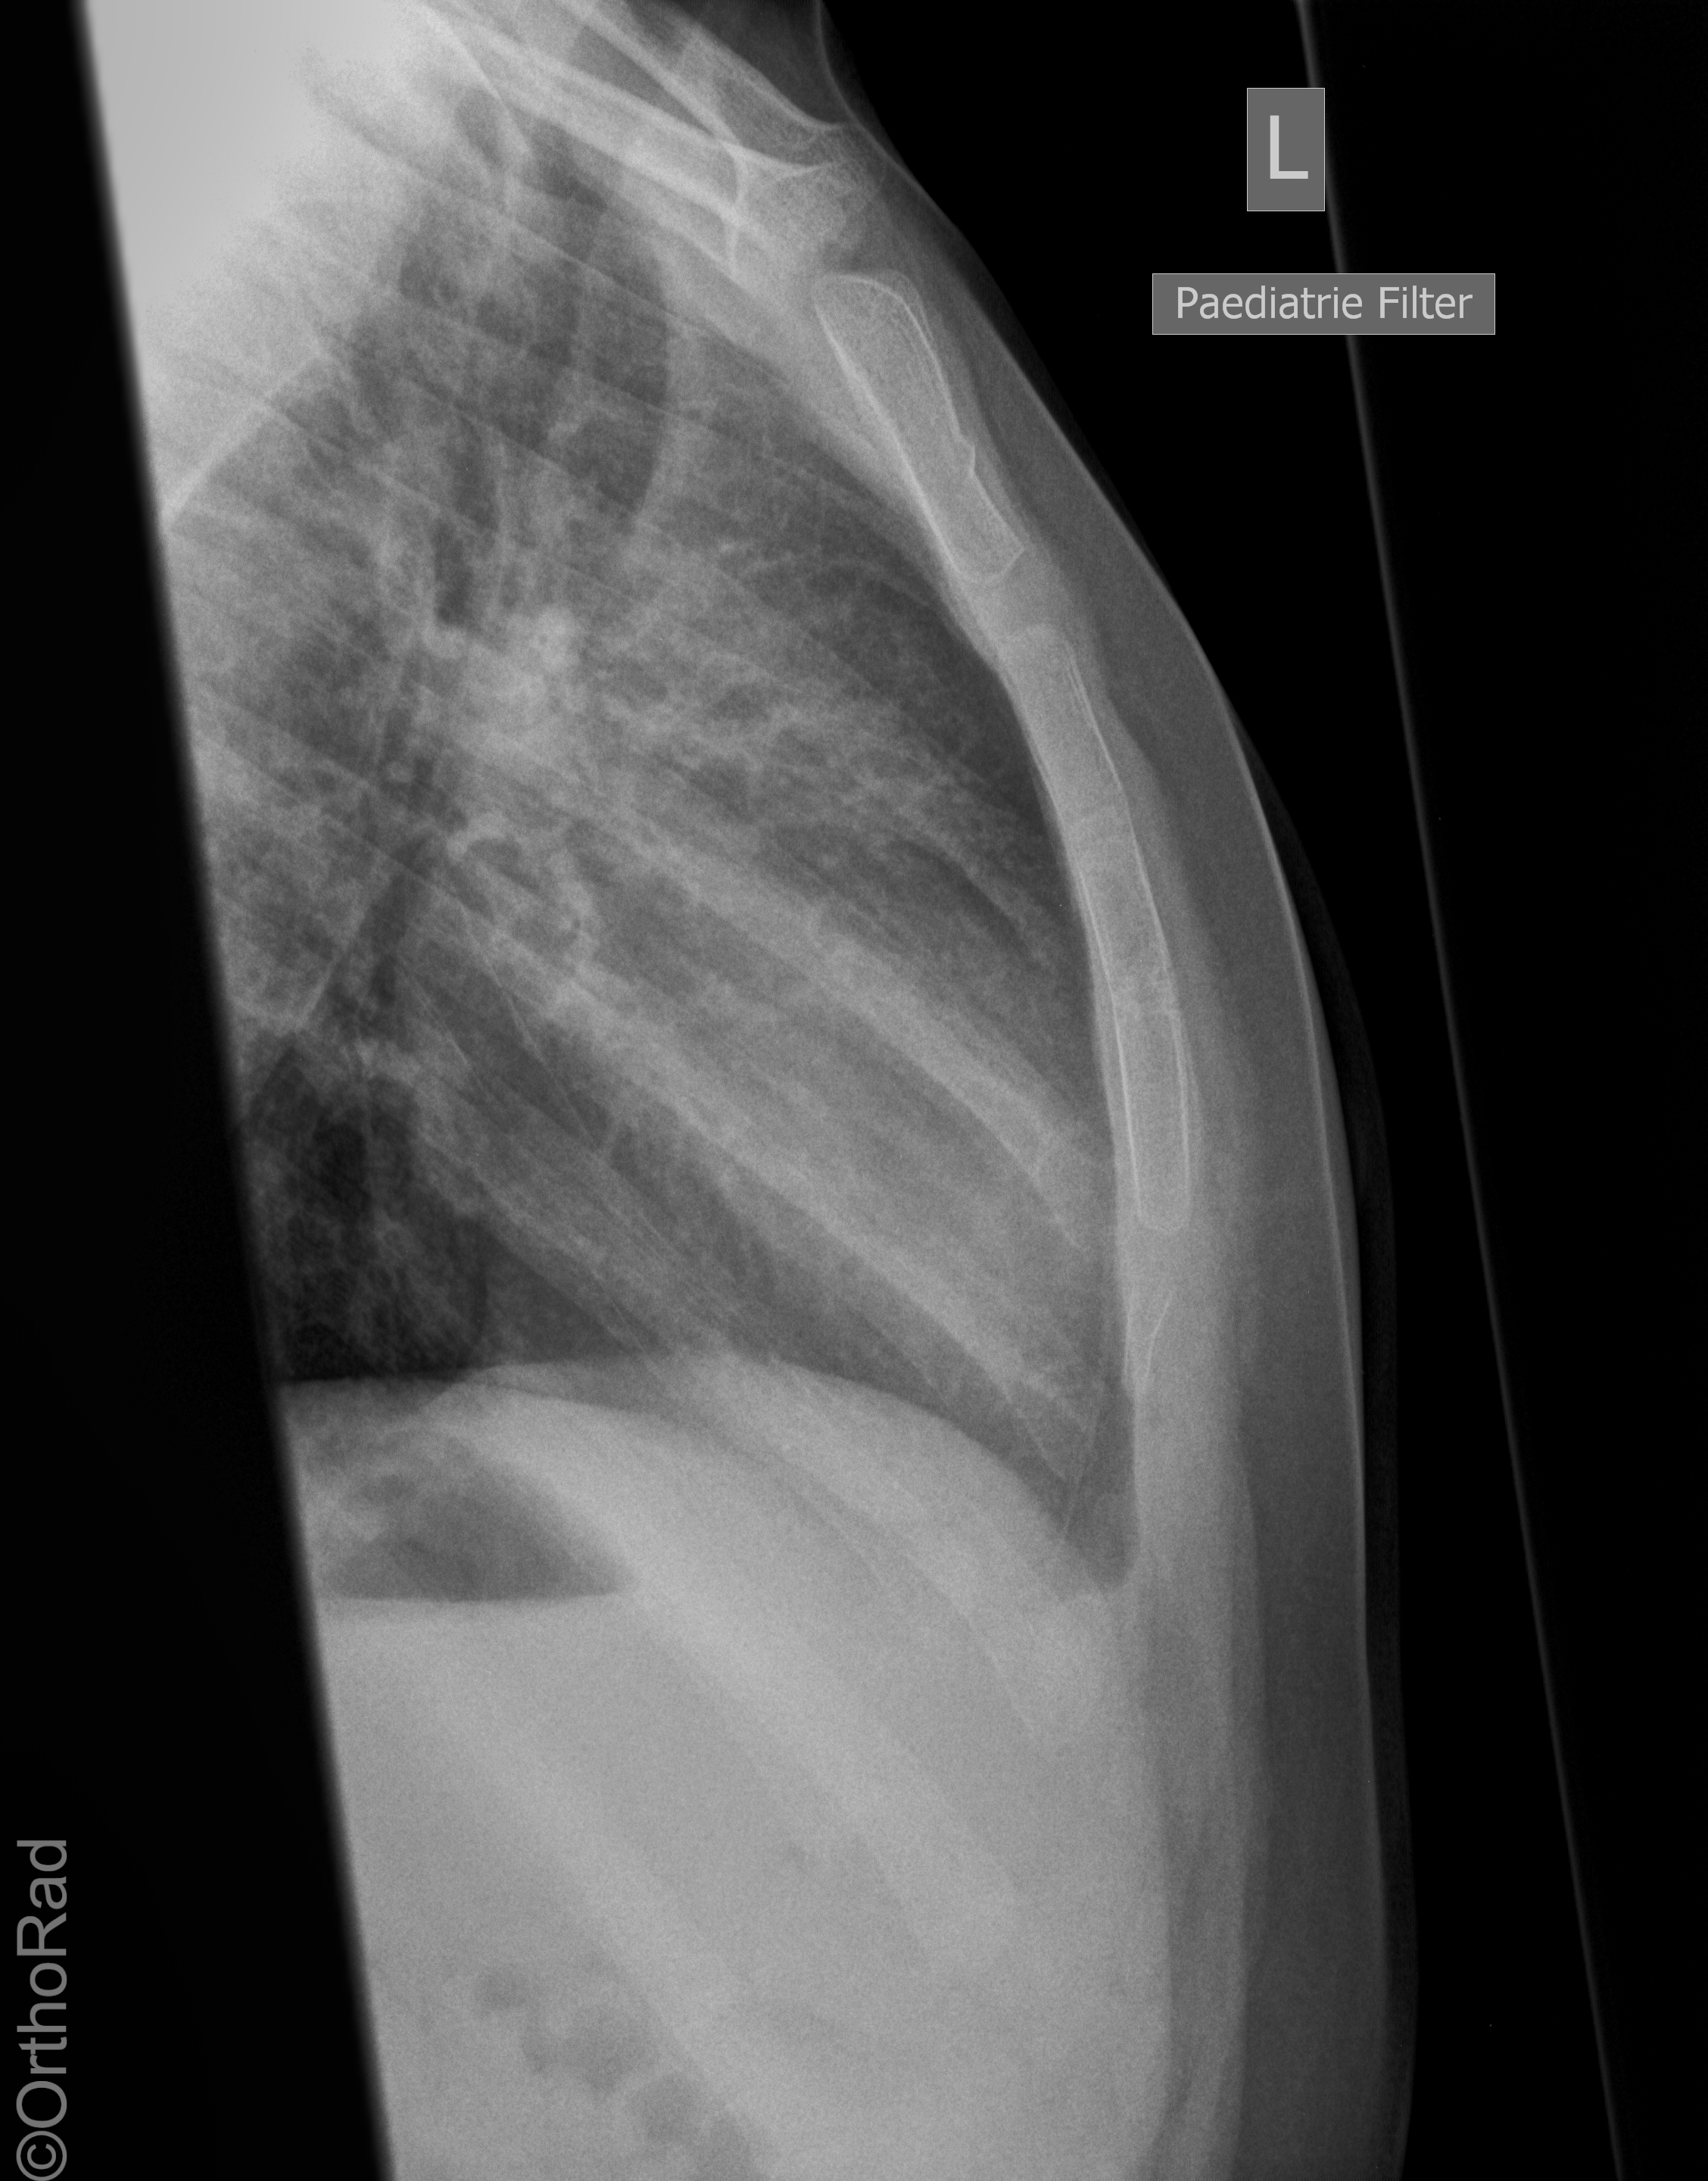

Wulstfraktur des Manubrium sterni